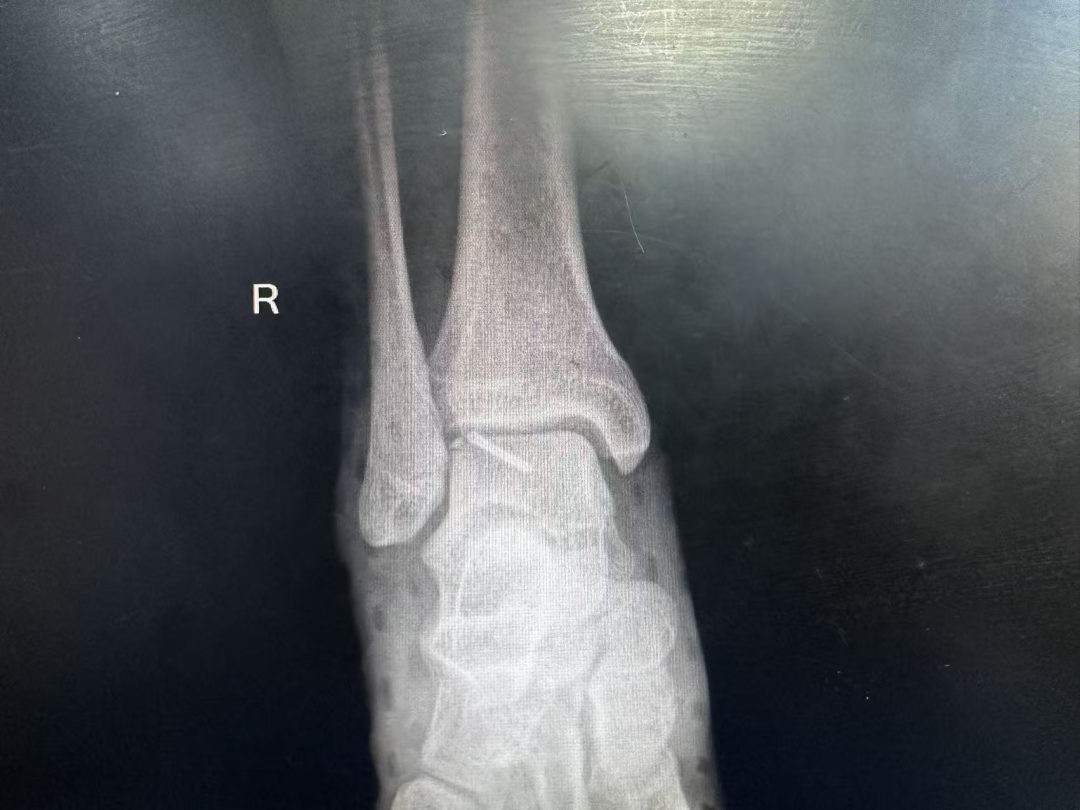

术后影像学检查 踝关节正位片

术后影像学检查 踝关节侧位片